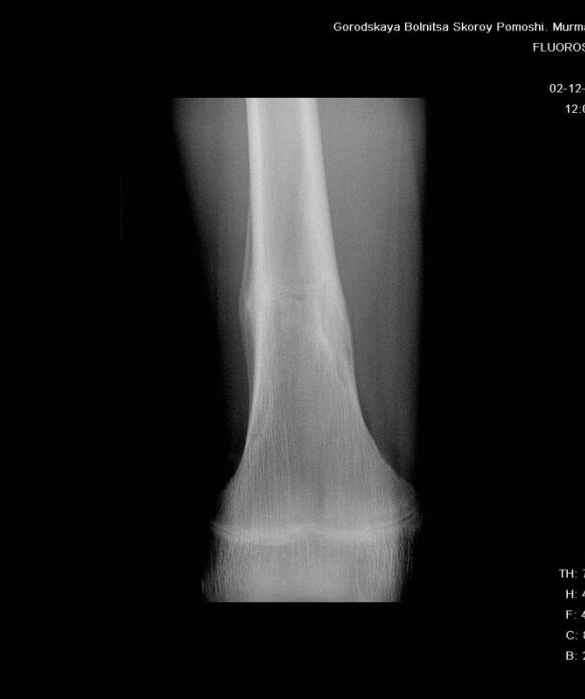

Анамнез практически никакой: в следствие травмы (растяжение связок коленного сустава) от 07.11.2004 выполнены Rg-граммы в травмпункте и обнаружено опухолевидное образование. Первичные Rg-граммы я не публикую, так как они заметно худшего качества, да и динамики за прошедшие три недели не отражают. Болевой синдром купирован в течение трёх дней. В настоящий момент мальчика ничего не беспокоит. Ходьба не нарушена, опухоль пальпируется с трудом по задней поверхности в н\3 правого бедра, пальпация безболезненна, объем движений в суставах правой нижней конечности полный и симметричный. Кожа над опухолью не изменена.В нашей клинике проведено дополнительное обследование: общие анализы крови и мочи, биохимия крови без особенностей. Выполнены Rg-граммы на цифровом Siemens обычные и продольные томограммы срезами 3-5 мм, а также компьютерная томография поперечными срезами по 5 мм. Прошу обратить внимание, что на приведённых томограммах видны две полости 10х15 мм и 15х60 мм. Также имеются два опухолевидных образований наслаивающихся друг на друга: уплощённое и вытянутое 10х100 мм и элипсовидной формы 15х30 мм. Это хорошо заметно на фото a_1.jpg c_1.jpg и d_1.jpg. Плотность внутри полостей 125% от плотности костномозгового канала, плотность наружного опухолевидного образования 55% от плотности кортикального слоя. Также отмечается линия перелома по центру наружного опухолевидного образования.Исходя из полученных данных мнения в плане диагноза несколько разделились от 1)сочетания кортикальной фиброзной дисплазии и латентно протекавшего маршевого перелома н\3 правого бедра до 2)остеосаркомы. В отношении первого варианта не сходится отсутствие клиники при переломе такой крупной кости как бедро, второй вариант вообще оставлю без комментария, ибо некомпетентен. Хотелось бы услышать мнения коллег, с удовольствием ознакомлюсь с любыми предположениями и замечаниями.С уважением, Александр Е. КлоковОтделение детской ортопедии и травматологииБСМП г. Мурманска.